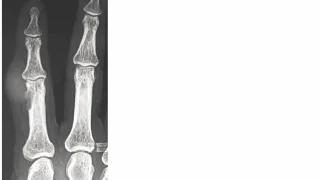

手術日+728日目 2026/2/25(水)(筋肉内神経鞘腫)